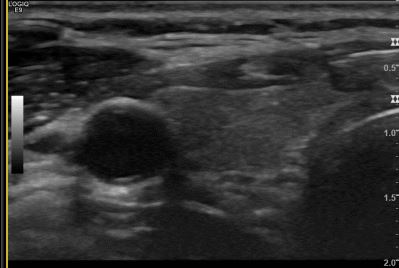

상기환자  외부검사이상소견으로 내원하신 40대 후반 여성분으로 의심스러운 갑상선 우측혹 세포검사진행후 갑상선암으로 진단되었습니다